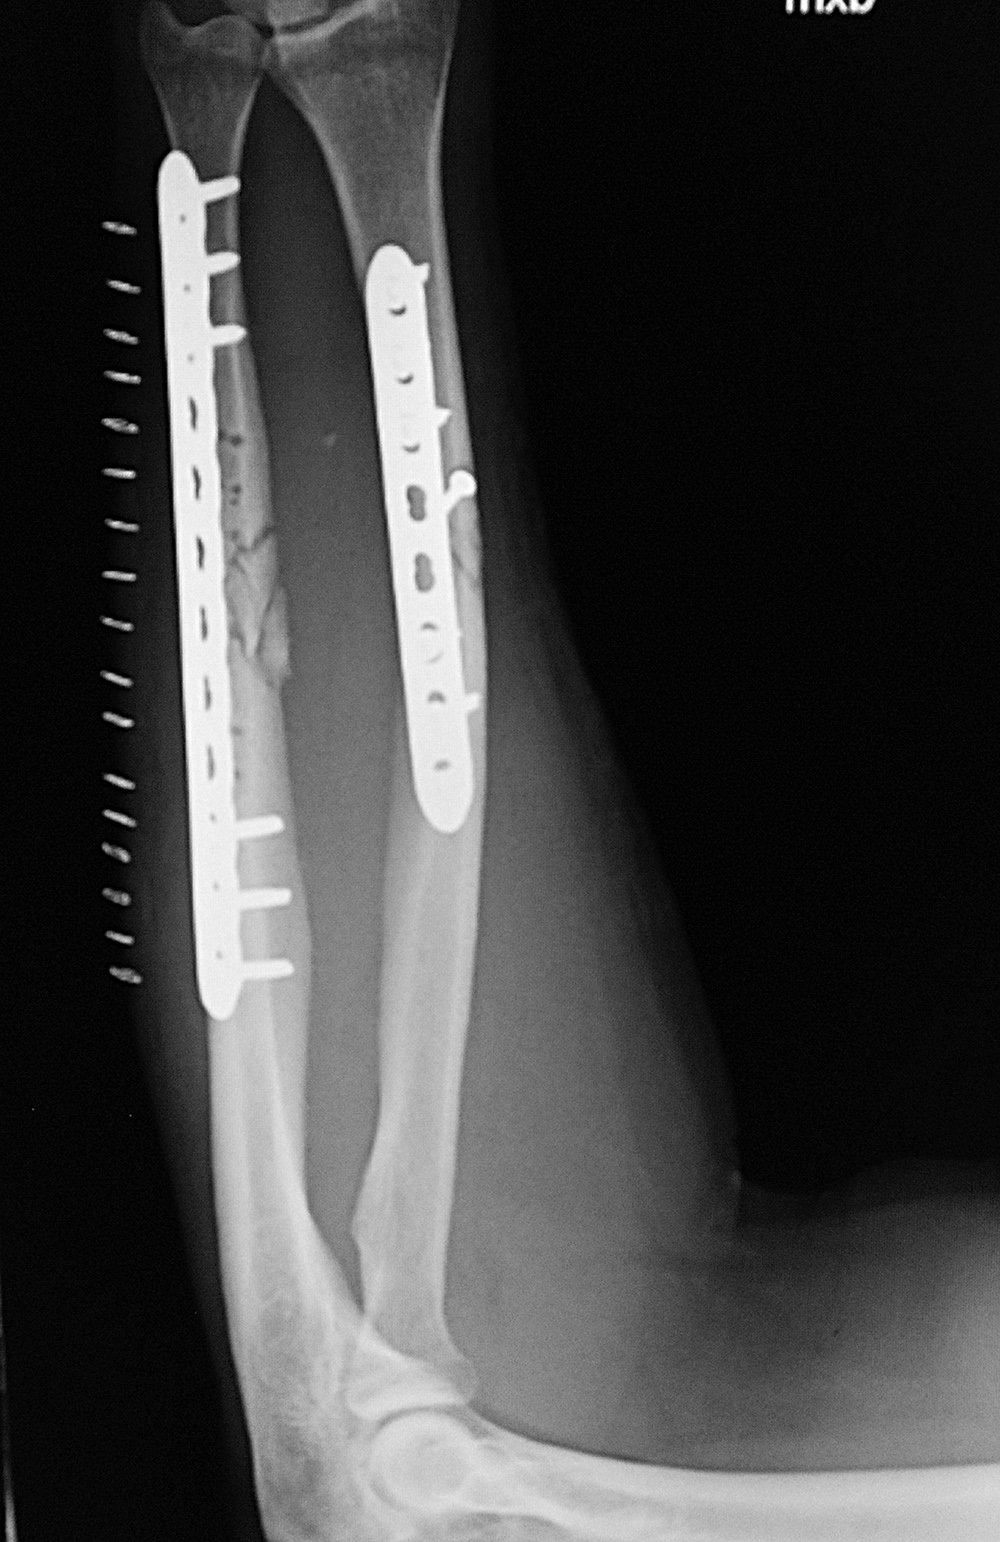

Left tibia stress fracture after fibular fracture fixation |

A short one-third tubular plate and screws plus interfragmentary screw stabilize a healing distal fibular fracture. An associated stress fracture (arrow) is in the distal tibial metaphysis from altered weight-bearing from the fibular fracture. |